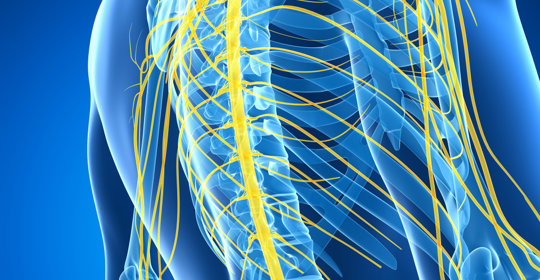

大腦與神經